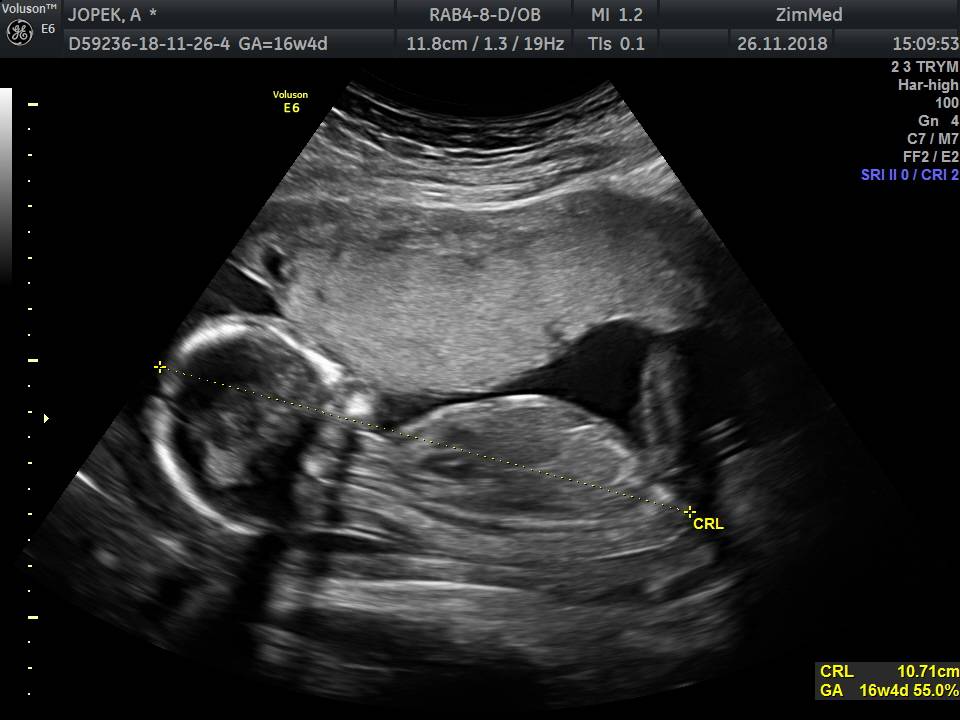

Nie mam nuba bo to juz 16tc wiec juz widac wszystko. Odstaje jak byk miedzy nogami jajka

IMG_20181126_1_7.jpeg

• IMG_20181126_1_7.jpeg

63,8 KB · Wyświetleń: 500